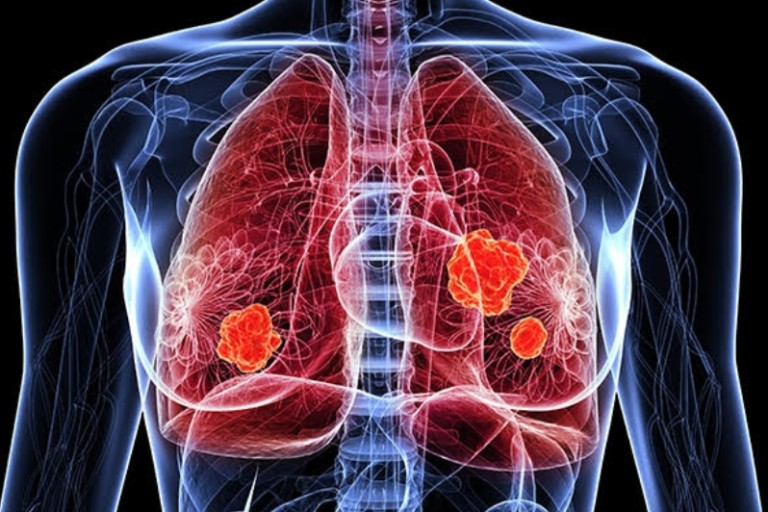

폐암은 위암, 갑상선암 다음으로 3번째로 발병 빈도가 높은 3대 암 중 한 가지입니다. 폐암은 재발과 전이까지의 빈도도 잦은지라 완치가 어렵다고 하며 폐암 발병 초기에는 거의 증상이 없을 수가 있어 수술이 불가능한 3기, 혹은 4기에 주로 진단된다고 합니다.

폐암 4기에 이르게 되면 5년 생존률이 30% 대로 떨어지게 된다고 합니다. 그리해서 폐암은 암 질병이자 중 사망자 비율이 가장 높은 것으로 나타나고 있습니다.

폐암은 사망률 2위를 차지하고 있는 간암에 비해 무려 2배에 가까운 사망률을 보이고 있다고 해요. 이렇게 치명적인 폐암에 대해 미리 알고 대처하는 것이 바람직할 것 같습니다. 아래에서는 폐암이라 판단해 볼 수 있는 그 초기증상에 대해 간단히 설명드리겠습니다.